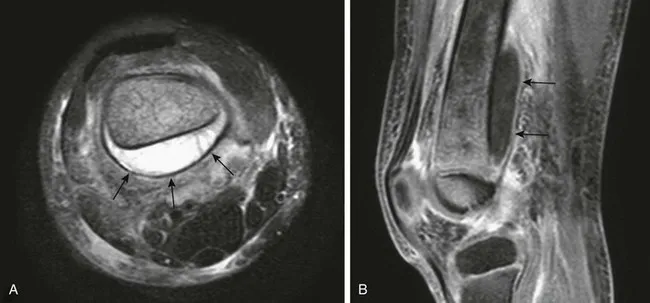

- Imaging: X-ray (late: periosteal reaction 10-14 days). MRI (best for early diagnosis). Ultrasound (subperiosteal abscess).

⭐ MRI is the most sensitive and specific imaging modality for early diagnosis of AHO, detecting changes within 24-48 hours of onset.